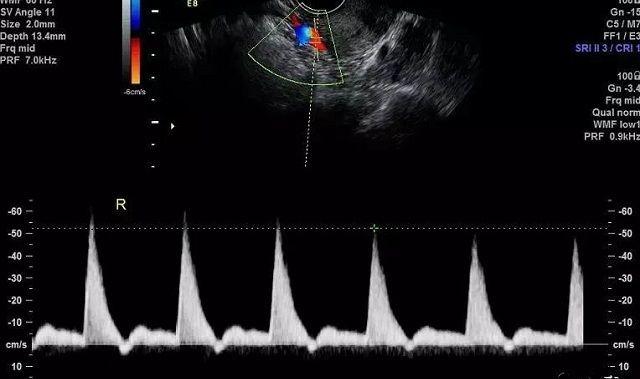

妇科超声检查一般包括经腹超声和经阴道超声。现在大部分医生对有性生活的女性和早孕期女性更愿意行经阴道超声检查。那么,经阴道超声检查较经腹部超声检查有什么优点?做经阴道超声检查会感染吗?早孕期经阴道超声检查会有辐射吗?对宝宝发育有影响吗?

1、阴道超声探头比腹部超声探头频率明显提高,图像更清晰,特别是对于腹部脂肪厚的女性,经腹超声由于腹部脂肪层对超声的吸收,可能会影响检查效果;所以经阴道超声的优势更加明显。

2、经阴道超声更接近盆腔脏器,可以提高诊断率;经阴道B超比经腹部B超能早一周发现宫内孕囊中的卵黄囊及胚芽组织。

阴道B超呈像示意图

做经阴道超声的医生在为每一位患者进行检查前,都会更换检查手套、消毒垫巾及检查所使用的避孕套,这些都是一次性的消毒用具,因此做经阴道超声一般不会增加感染阴道炎的风险,大家可以放心的选择经阴道超声检查。